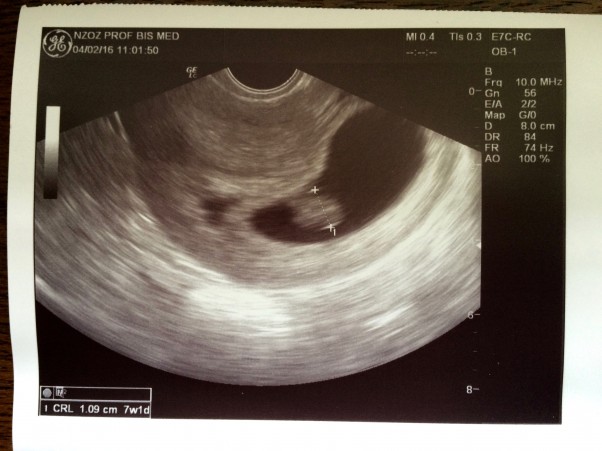

Dziś miałam drugą wizytę u ginekolog.

Zrobiła usg i "postraszyła" ciążą bliźniaczą, ale pokazała tylko jeden zarodek i serduszko. Nie była pewna co do tej plamki po lewej stronie. Ja sądzę, że to krwiak:P